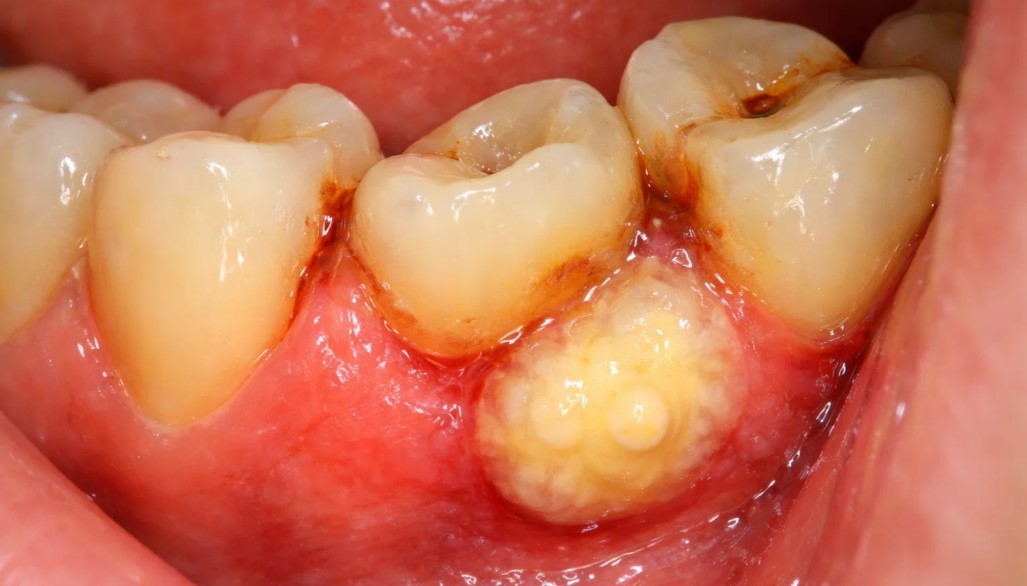

A dental abscess is a pocket of pus caused by a bacterial infection. It usually forms when bacteria enters the tooth through a cavity, crack, fracture or advanced gum disease.

- Periapical abscess: Infection at the tip of a tooth root

- Periodontal abscess: Infection in the gum tissue near a tooth